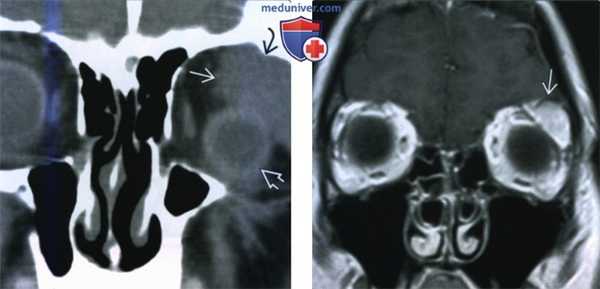

(Слева) При КТ с КУ в аксиальной проекции определяется несколько гетерогенное контрастное объемное образование с четкими контурами. В ткани опухоли часто обнаруживается мелкая киста. Обратите внимание на неизмененную контрлатеральную слезную железу.

(Справа) При аксиальной КТ без контрастного усиления определяется дольчатое объемное образование левой слезной железы с четкими контурами, содержащее в своей задней части кальцинаты. (Слева) При корональной КТ без контрастного усиления в верхневисочном отделе левой глазницы определяется дольчатое объемное образование, сопровождающееся «фестончатой» перестройкой кости ямки слезной железы. Обратите внимание на характерное смещение глазного яблока, вызываемое опухолями области слезной железы.

(Справа) При МРТ Т1 с КУ в корональной проекции в верхнелатеральной части левой глазницы визуализируется контрастируемое объемное образование с четкими контурами, вызывающее ровную «фестончатую» перестройку кости.

(Справа) При аксиальной КТ без контрастного усиления определяется дольчатое объемное образование левой слезной железы с четкими контурами, содержащее в своей задней части кальцинаты.

(Слева) При корональной КТ без контрастного усиления в верхневисочном отделе левой глазницы определяется дольчатое объемное образование, сопровождающееся «фестончатой» перестройкой кости ямки слезной железы. Обратите внимание на характерное смещение глазного яблока, вызываемое опухолями области слезной железы.